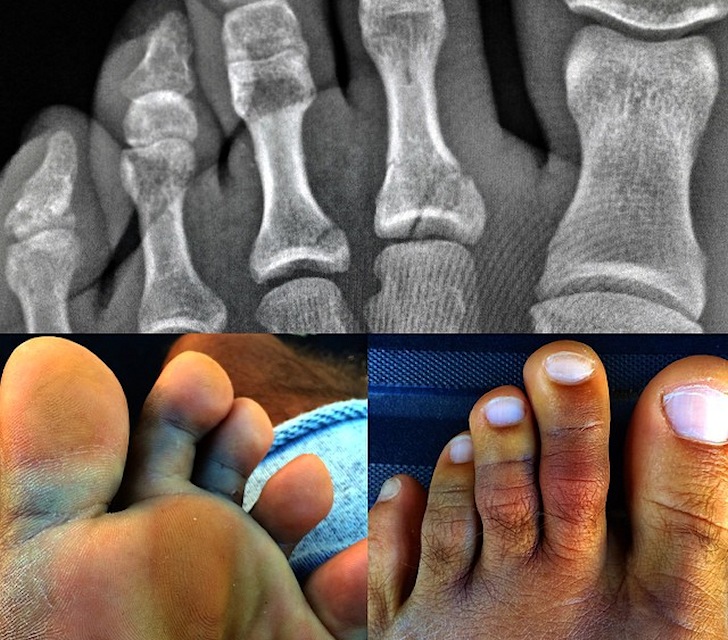

Kelly Slater has broken a bone on the second and third toes of his left foot, but the champion won’t miss the 2014 Billabong Pipeline Masters. The 11-time world surfing champion is keeping his eyes on the title race, despite suffering an injury while riding waves at Cloudbreak, in Fiji. “The foam ball from the lip landing inside the barrel bounced back up and flipped the board into my foot, hyper-extending the toes backwards,” explains Kelly Slater on his Instagram feed.